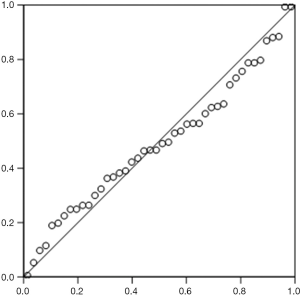

According to the standardized residuals histogram, the standardized residuals of these measurements were normally distributed (Figure 2). According to the normal P-P plot of regression standardized residual, the points in the graph were basically located in one straight line. Thus, the equation was proven to be statistically significant (Figure 3).

Our study also found that pleural effusion at an amount of 500–1,000 mL was significantly correlated with the maximum depth and maximum thickness at the subscapular line but not with the maximum depths at other lines. In contrast, Shen et al. found that the pleural effusion amount was positively correlated with the maximum depth under US but was not significantly correlated with the number of rib spaces, number of longitudinal zones, and sequence of drainage (14). The maximum thickness was employed as a coefficient in our equation because the maximum depths at all these five lines showed no statistical significance in patients with a pleural effusion amount of smaller than 500 mL or between 500 and 1,000 mL. In addition, we divided the actual pleural effusion amount into three groups to make the estimation results more accurate. According to the standardized residuals histogram, the standardized residuals of these measurements were normally distributed, which demonstrated the statistical significance of the equation. Our study was limited by its relatively small size. Also, the actual pleural effusion amount affects the depth of US measurement. If the pleural effusion amount is too small or too large, the measurement for the depth will yield an accurate result, which further affects the accuracy of the equation. Further study is warranted to confirm whether the US measurement equation is feasible for patients with a small/large amount of pleural effusion.